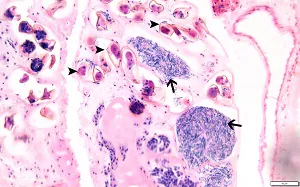

Philophthalmiasis image

Figure A: Longitudinal section of Philophthalmus sp. (likely P. gralli), H&E stained. Note the large oral sucker (arrow) and ventral sucker/acetabulum (dart).

Figure B: Closer view of the longitudinal section in figure A, showing eggs (darts) within uterine loops, and spermatic tissue (arrows).